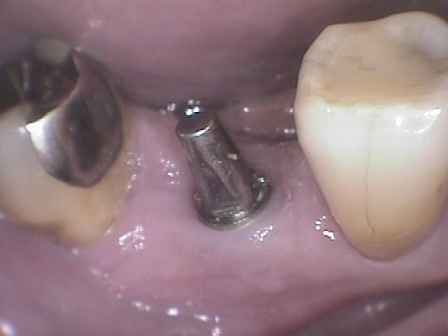

症例2

右下 6 番単独欠損ですが、中等度歯周病(水平的骨吸収あり)のため、ブリッジでの治療ですと隣接歯の寿命を極端に縮めてしまう可能性があります。